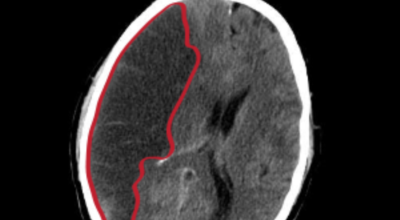

막힌 혈관으로도 혈액이 공급되긴 하나 혈관이 막혀있어 혈액을 보내긴 하나 제대로 흐르지 못하고 혈액이 쌓이고 축적되어 물풍선에 물이 꽉 차서 터지듯 뇌혈관이 터지는 경우가 일어날 수 있는데 이를 뇌출혈 이라고 해요. 물론 외상으로 인한 뇌출혈도 있지만 이처럼 뇌경색으로 인해 혈관이 막혀 터지는 경우도 있어요.